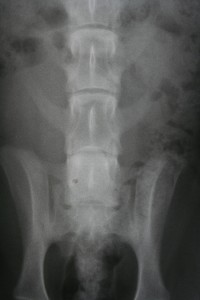

Лечение межпозвоночной грыжи в ИзраилеМежпозвонковая грыжа является главной причиной боли в позвоночнике. Любой внутренний орган или его часть, превышающую нормальные анатомические нормы, называют грыжей, а межпозвонковая грыжа представляет собой часть межпозвонкового диска, вышедшую за его пределы. Ежегодно сотни пациентов проходят успешное лечение грыжи позвоночника в Израиле и уверенно чувствуют, что боль проходит быстро, не возвращаясь вновь.

Межпозвонковый диск – это волокнисто-хрящевая пластинка с ядром в середине. Если уменьшить поступление жидкости в ядро, амортизирующая функция даёт сбой, и диск начинает выступать, провоцируя дистрофию мышц, окружающих позвоночник.

Грыжа может возникнуть при одновременном наклоне и повороте. Шансы заметно возрастают, если держать в руках что-то тяжёлое. В таком положении происходит перегрузка межпозвоночных дисков, ядро смещается и давит на фиброзное кольцо. Оно, в свою очередь, также не выдерживает нагрузки, и таким образом происходит выпячивание диска, которое может привести к сильным болям и нарушениям работы внутренних органов. Ситуация может обрести действительно серьёзный характер, если выпячивание произошло в сторону спинного мозга. В этом случае, возможно, его повреждение и даже летальный исход.